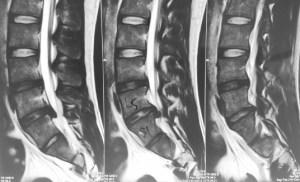

This is a patient who presented with sciatica in his left leg from a L5/S1 posterolateral left sided slipped disc in 2012.

He was offered surgery but chose conservative treatment.

His pain eventually resolved over a period of 3 to 6 months after taking medications and undergoing intensive physiotherapy.

The same patient underwent a new MRI scan of his lumbar spine in 2015 for lower backache. There was no sciatica in his lower limbs.

The MRI showed resorption of the previous large left sided slipped disc.